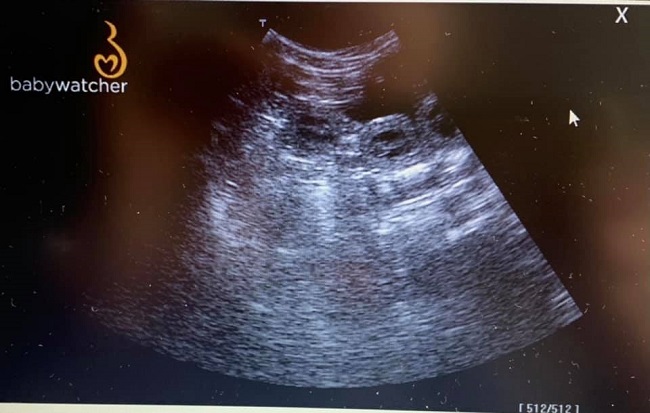

24.02.2021 Ultraschall am 32. Tag der Trächtigkeit

Ein erneuter Ultraschall zuhause, ganz entspannt zeigte zahlreiche kleine Passagiere in Melodies Bauch, dicht an dicht gekuschelt <3